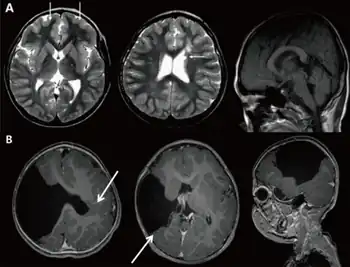

| a) Brain magnetic resonance imaging with global developmental delay (and increased serum creatine kinase) b) global developmental delay (and left hemiplegia ) | |

- Targeted MRI brain can be considered second line in selected patients, and is more likely to contribute to a diagnosis if the child has abnormal physical signs such as microcephaly, macrocephaly, a change in head circumference, focal neurological signs, or epilepsy.